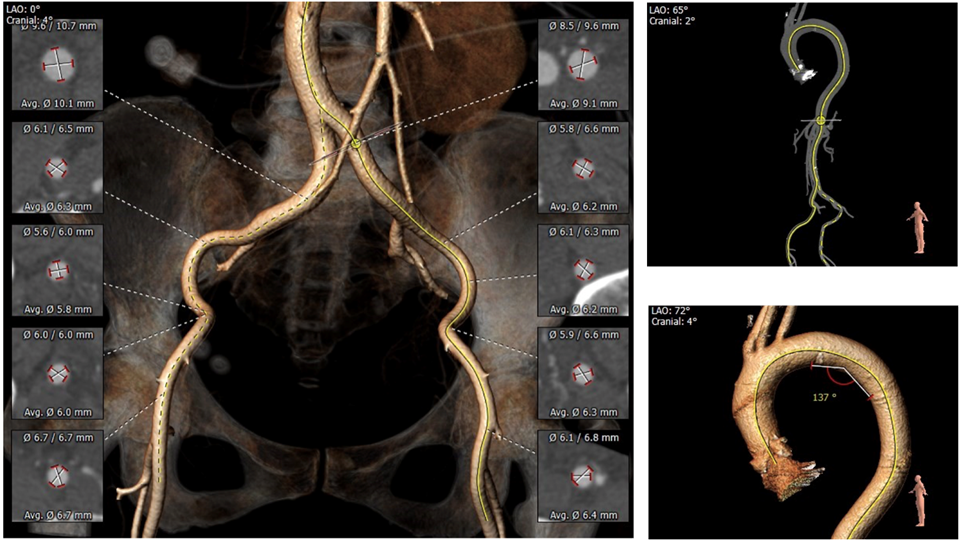

1.主动脉瓣瓣环周长77.8,平均周长径24.1。

2.主动脉瓣成三叶式,瓣叶增厚并伴有四级钙化,钙化分布不均匀,左无交界处钙化融合形似嵴并延伸至血管壁。

3.左右冠脉开口高度可,冠状动脉钙化严重。

5.双侧股动脉入路血管管径良好,少量轻微钙化,内径最窄处近临界值。

主动脉根部评估:

瓣环上解剖结构评估:

外周血管及主动脉弓解剖:

4. 根据术前CT评估,跨瓣角度为LAO 12° CAU 5°(右窦中心位)左右,球囊预扩角度为LAO 32° CRA 2°(左冠切线位)左右,释放角度为RAO 16° CAU 24°(左右重合)左右。使用20mm球囊预扩,根据沛嘉TaurusOne®产品设计特点采取瓣环平面下2-4mm高度释放策略。